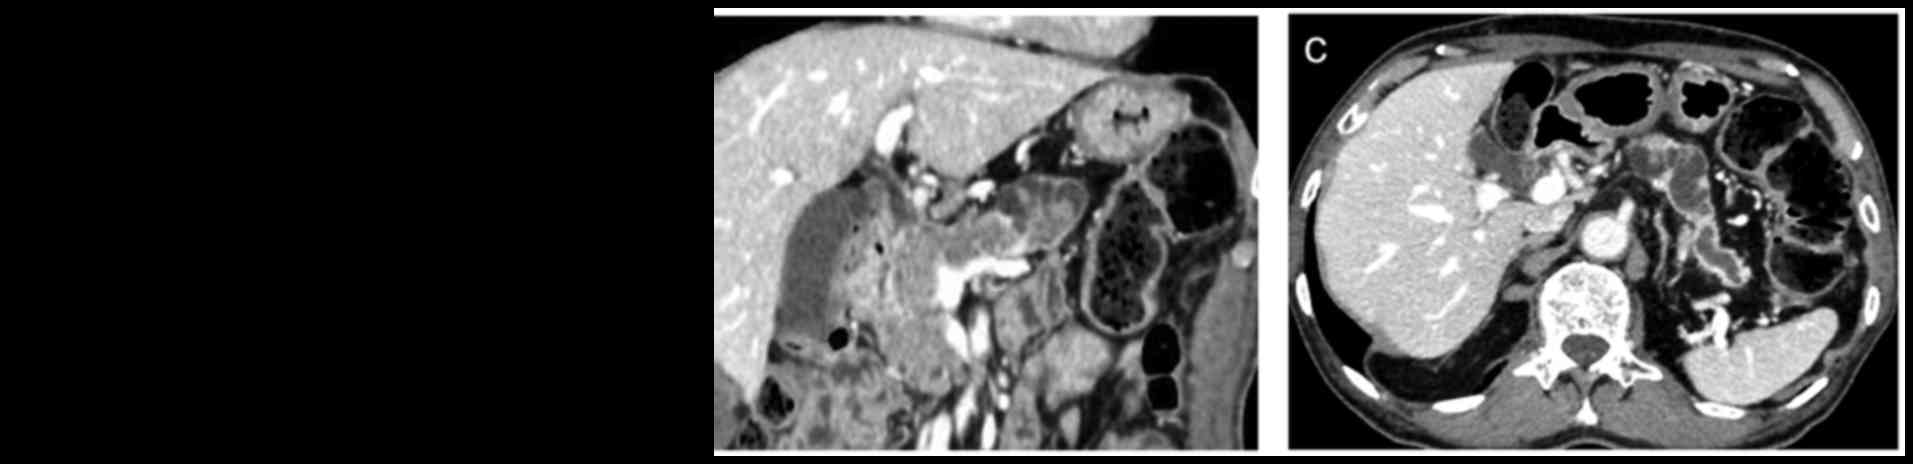

A 74-year-old male was admitted to the Departments of Surgery, Toyonaka Municipal Hospital (Osaka, Japan) for treatment of a pancreatic tumor. The patient's medical history included alcoholic acute pancreatitis, a renal stone and cerebral infarction. The patient did not exhibit any significant findings on physical examination. The laboratory analysis results were within the normal range, with the exception of the serum glucose level (155 mg/dl; normal range 60–110 mg/dl) and HbA1c-NGSP (7.0%; normal range 4.6–6.2%), which were elevated. The levels of various tumor markers were within the normal range, including carcinoembryonic antigen (2.8 ng/ml; normal range, <5.0 mg/dl), cancer antigen 19-9 (15 U/ml; normal range, <37 U/ml), s-pancreas-1 antigen (8.6 U/ml; normal range, <30 U/ml) and duke pancreatic monoclonal antigen type 2 (46 U/ml; normal range, <150 U/ml), and the serum IgG4 level was also normal (42.8 mg/dl; normal range, 4.8–105 mg/dl). Contrast-enhanced computed tomography (CT) revealed a mass with small cystic lesions in the pancreatic head and body that exhibited a non-uniform contrast effect (Fig. 1A and B). The main pancreatic duct at the peripheral side of the mass was dilated to 18 mm (Fig. 1C). Although the patient was not jaundiced, the lower common bile duct was surrounded by the mass, which was in contact with the portal vein and the superior mesenteric vein. There were no visibly enlarged lymph nodes. Magnetic resonance imaging (MRI), as with CT, revealed small cystic lesions in the mass on T2-weighted images (Fig. 2A). The mass in the pancreatic head and body was visualized with high signal intensity on diffusion-weighted images (Fig. 2B). On MR cholangiopancreatography (MRCP), there were small cystic lesions present in the mass and dilatation of the main pancreatic duct from the pancreatic body to the tail (Fig. 2C). Upper gastrointestinal endoscopy revealed rough mucosa near the opening of the accessory pancreatic duct and no mucus was observed (Fig. 3A). Biopsy of the mucosa revealed adenocarcinoma. An 18F-fluorodeoxyglucose (FDG)-positron emission tomography scan revealed abnormal FDG uptake with a maximum standardized uptake value of 4.9 for the mass (Fig. 3B). Based on the aforementioned findings, the pre-operative diagnosis was pancreatic ITPN with associated cancer lesions. Although IPMN was also considered as another possible differential diagnosis of the mass, this diagnosis was rejected due to the lack of mucous secretion identified. A laparotomy using an upper and middle abdominal median incision was performed under general anesthesia. The whole pancreas was hard, likely due to the patient's previous pancreatitis. As the mass was located in the entire pancreatic head and body, an attempt was made to resect the pancreas on the tail side of the mass, in order to preserve the pancreatic tail. However, it was problematic to separate the pancreatic body and the splenic artery and vein, due to the tissue hardness. Therefore, it was judged to be impossible to preserve the spleen, and a total pancreatectomy with splenectomy was subsequently performed. Lymphadenectomy was performed for dissecting regional lymph nodes. Macroscopic examination of the resected specimen indicated an off-white solid tumor occupying the entire pancreas with intraductal growth of the main pancreatic duct; mucin was not identified (Fig. 4A and B). Histological examination using hematoxylin and eosin staining revelaed that the tumor exhibited high-grade dysplastic cells in a tubulopapillary growth pattern without the overt production of mucin (Fig. 4C and D). The tumor had infiltrated the main pancreatic duct, although the pre-operative CT scan had not revealed any tumors in the main pancreatic duct of the pancreatic tail. The tumor had invaded beyond this to the entire pancreatic parenchyma and serosal invasion and retroperitoneal invasion were observed, whereas vascular invasion was not identified. Among 30 lymph nodes dissected, metastasis was verified to be present in two lymph nodes. The metastases were also identified in the lymph nodes along the common hepatic artery and the splenic artery. No cancer cells were identified in the resected cut end margin of bile duct or dissected peripancreatic tissue. Immunohistochemical staining was positive for cytokeratin (CK)7 (Roche Diagnostics, Basel, Switzerland), CK19 (Leica Microsystems, Ltd., Milton Keynes, UK) and mucin (MUC1) (Leica Microsystems Ltd.), and negative for MUC2 (Leica Microsystems, Ltd.), MUC5AC (Leica Microsystems, Ltd.), MUC6 (Leica Microsystems, Ltd.) and caudal type homeobox 2 (Biocare Medical, LLC., Concord, CA, USA; Fig. 5). The final diagnosis was determined to be pancreatic ITPN with associated invasive cancer. The patient progressed without post-operative complications. Following the surgery, the serum glucose levels were managed with subcutaneous insulin injections. At the time of this report (9 months post-surgery), the patient remains disease-free without evidence of recurrence, and is being followed on an outpatient basis (follow-up is ongoing for 5-years).

Figure 1.

Preoperative radiological imaging using enhanced abdominal CT. (A and B) CT images revealed a mass with small cystic lesions in the pancreatic head and body (A, axial scan; B, coronal scan). (C) The main pancreatic duct at the peripheral side of the mass was dilated to 18 mm. CT, computed tomography.